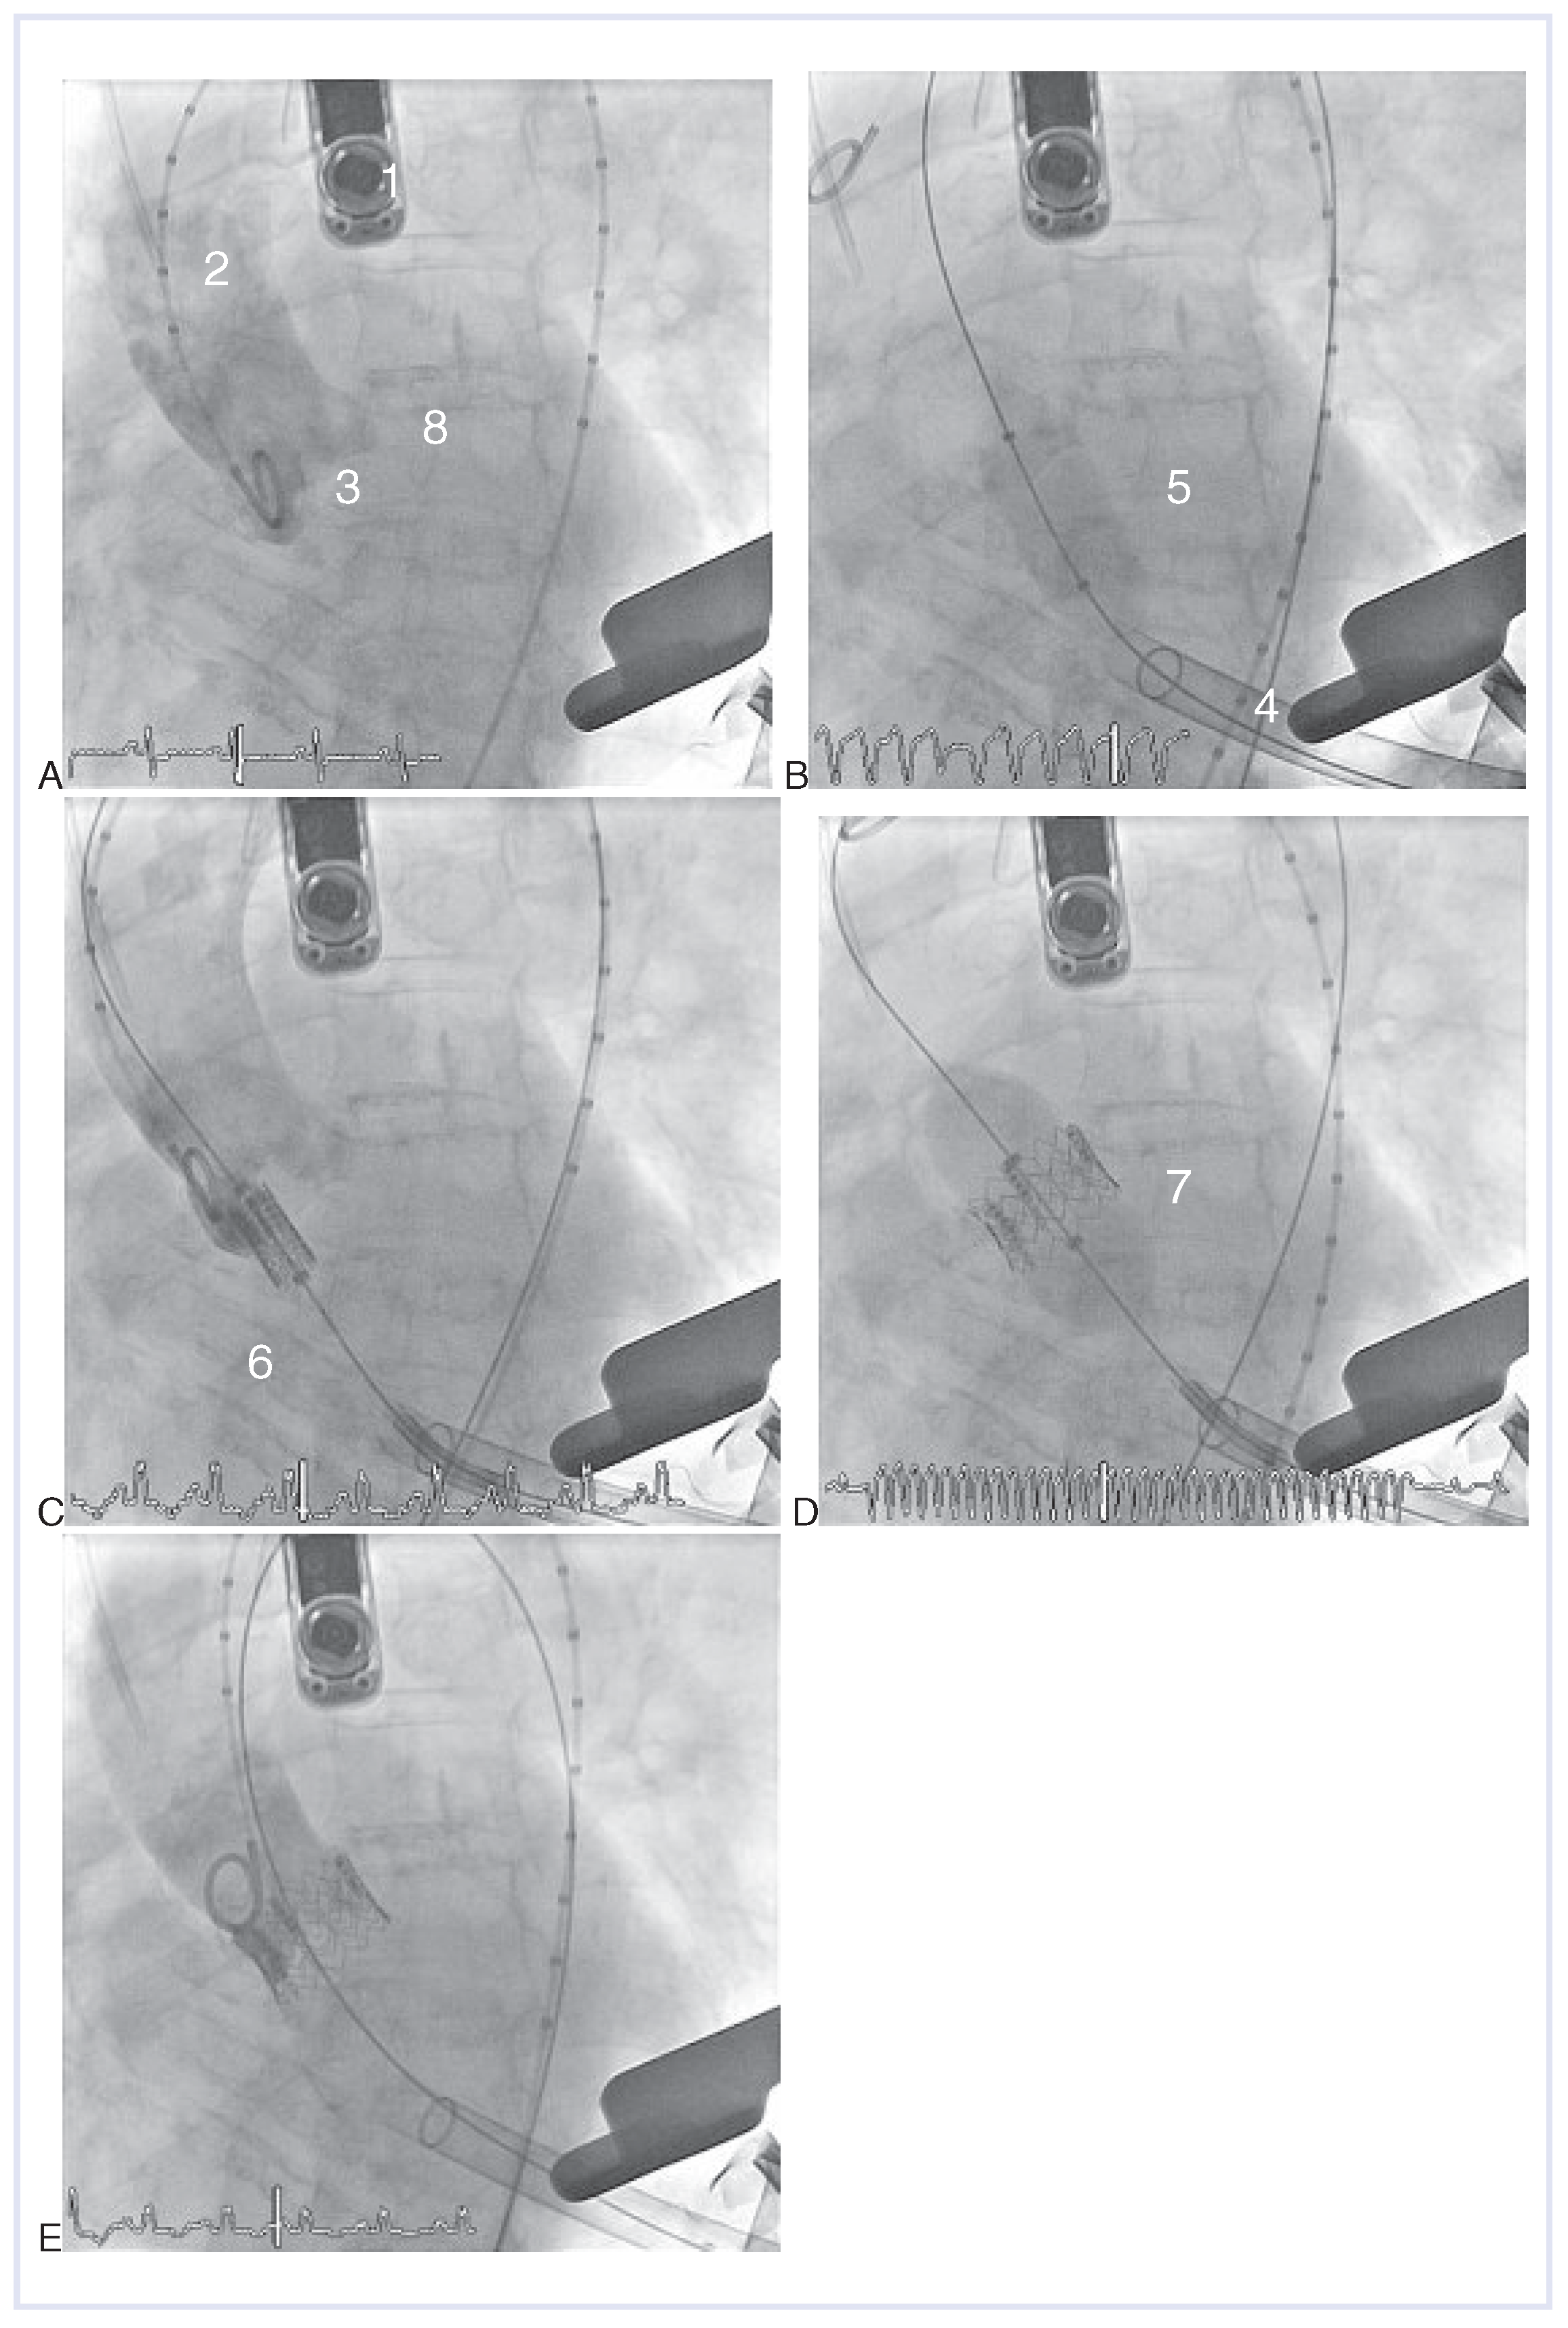

Abbildung 3. Transapikale Implantation einer Edwards-Sapien-Bioprothese (AE). (A) Aortographie. (B) Vordilatation unter rapid pacing. (C) Positionierung der auf den Einführungskatheter geladenen Bioprothese. (D) Klappenimplantation mittels Ballon-Inflation unter rapid pacing. (E) Kontrollangiographie nach Implantation. 1 Transösophageale Echokardiographie-Sonde; 2 Pigtail-Katheter; 3 Aortenklappenannulus; 4 transapikale Einführungsschleuse; 5 Edwards-Ballon zur Vordilatation der Aortenklappenstenose; 6 Edwards-SAPIEN-Klappe geladen auf Einführungskatheter; 7 Entfaltete Prothese mit Implantationsballon; 8 Implantierte Aortenklappenprothese nach Zurückziehen des Implantationsballones.